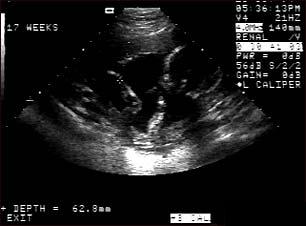

Ecografia fetala